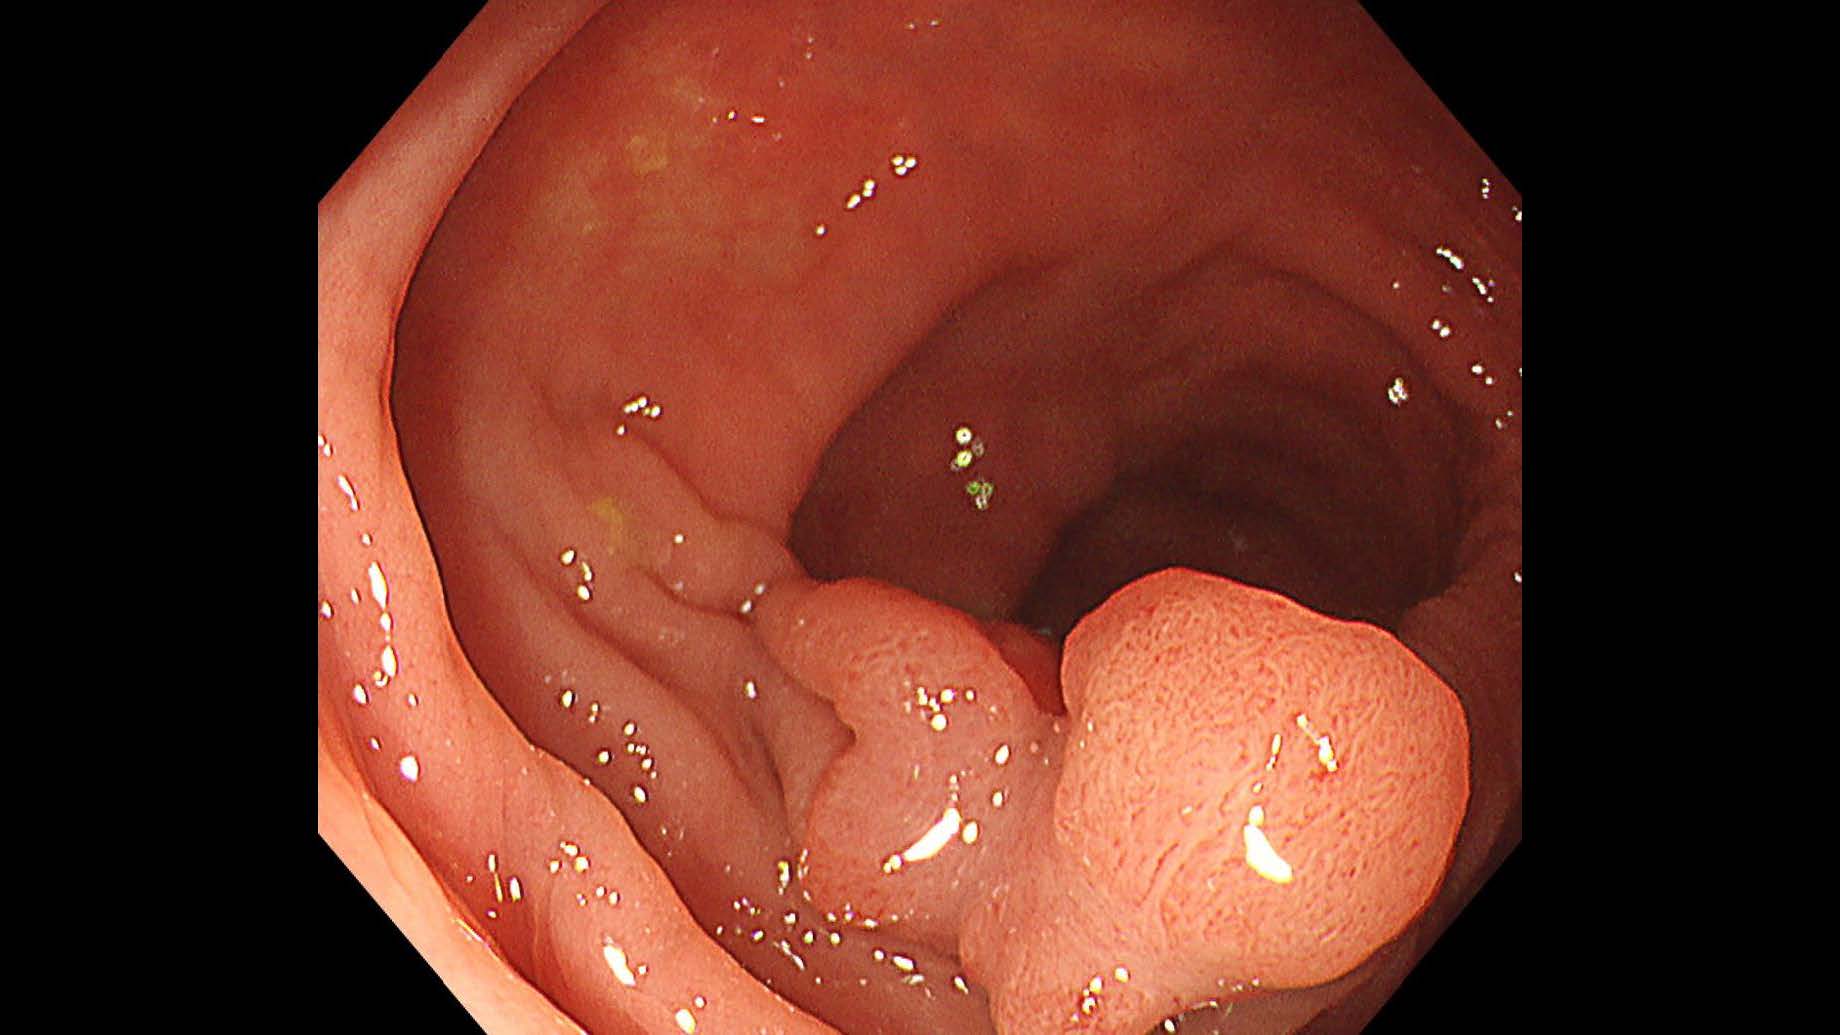

消化管Mapping~大腸~ 2025.6.11

消化管Mapping